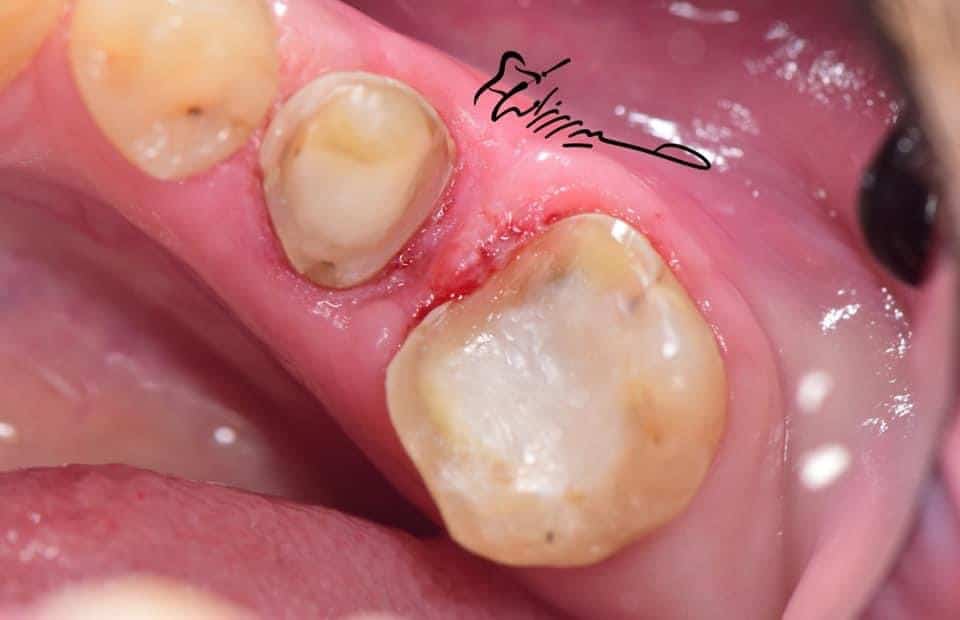

After removing the old restoration,

the tooth was dying ! And the margin level below the bone level!

Healing after surgical crown lengthening